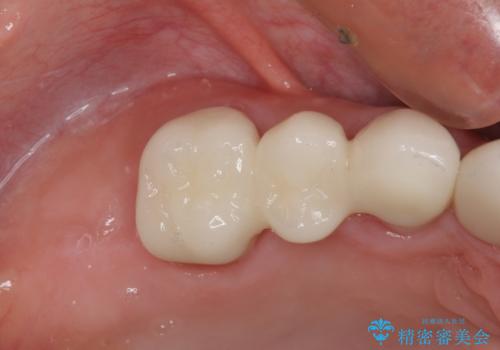

- 虫歯や歯の欠損を放置していることを気にして来院された患者様です。

下顎には抜歯が必要な歯があったため、抜歯後に治癒を待ち、上顎とともにオールセラミックブリッジにて補綴治療を行うこととしました。

治療開始の日に欠損部も含めて仮歯が装着され、今までの不具合や不快感があっという間に改善されました。

抜歯部位の治癒を待つために時間がかかりましたが、来院回数は数回で済み、患者様には大変満足していただきました。